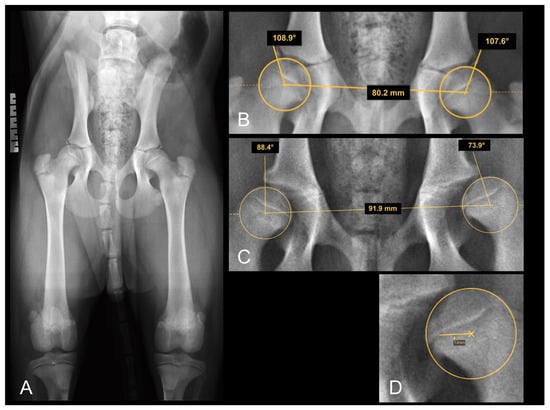

2.5.5. The Distraction Index (DI)

To quantify the DI, ventrodorsal distraction view radiographs (Badertscher method modified by Vezzoni) were taken, and the calculation of the DI was performed using the PennHIP measurement method [26]. The DI is calculated by dividing the distance between the centers of the femoral head and acetabulum by the radius of the femoral head during distraction and is a number between zero (healthy hip) and one (severe laxity). The incidence of hip laxity in dogs with DI ≤ 0.3 and DI ≥ 0.6 is reported to be low and high, respectively [34]. The measurement of the DI on the distraction view radiograph is shown in Figure 2.

Figure 2. (A) Distraction view VD radiograph of a four-month-old Rottweiler (same dog as in Figure 1A,B). (B) A magnification of the right and (C) a magnification of the left hip joint demonstrating the distraction index measurements. Note the laxity in the left joint which was not obvious in the extended view.